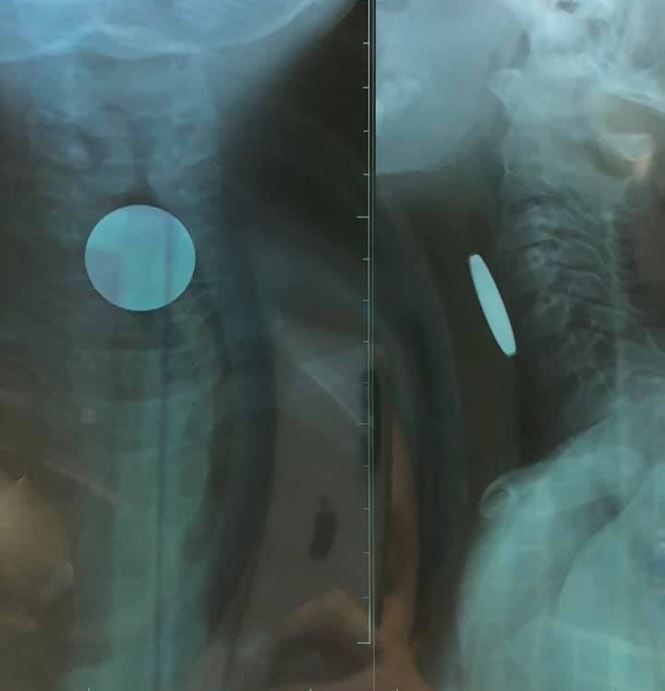

Chiều 2/6, thông tin từ Bệnh viện Hữu nghị Việt Nam - Cu Ba Đồng Hới (Quảng Bình) cho biết, các bác sỹ tại bệnh viện này vừa tiến hành nội soi thực quản gây mê, gắp thành công dị vật trong thực quản của một bệnh nhi 5 tuổi.

Cháu bé này là Nguyễn Hàn T. P. (SN 2014), trú phường Bắc Lý, TP Đồng Hới. Người nhà cháu P. cho biết, cháu lấy đồng xu dùng để chơi game ở siêu thị về nhà, trong lúc chơi đùa đã ngậm đồng xu trong miệng và nuốt, sau đó xuất đau vùng cổ nên nhập viện cấp cứu.

Qua thăm khám và chụp X-quang, các bác sỹ phát hiện có dị vật (đồng xu) đoạn thực quản cổ có đường kính 24mm. Sau khi tiến hành nội soi dưới gây mê và gắp đồng xu ra, bệnh nhi P. đã ổn định và có thể xuất viện.

Bác sĩ Nguyễn Hoàng Tùng, Khoa Tai- Mũi-Họng, Bệnh viện Hữu nghị Việt Nam - Cu Ba Đồng Hới, người trực tiếp gắp đồng xu trong thực quản cháu P. cũng khuyến cáo, các bậc phụ huynh không nên cho trẻ nhỏ cầm nắm trong tay những đồ vật nhỏ, vì theo phản xạ và thói quen, các cháu thường cho vào miệng và nuốt. Nếu không xử lý kịp thời sẽ nguy hiểm đến tính mạng, nhất là dị vật đường hô hấp.